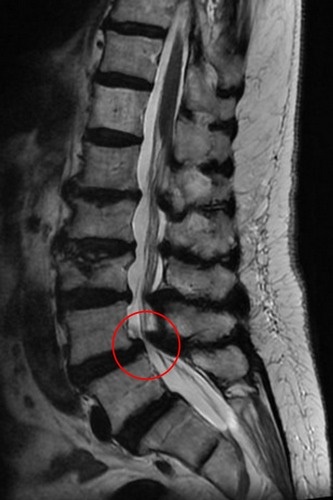

右圖:磁振造影顯示腰椎滑脫後因骨刺壓迫造成神經狹窄。

經考慮患者意願,在與家屬溝通後,由麻醉團隊為患者安排心臟超音波、頸部超音波、神經傳導等檢查評估風險,洪祥益主任帶領團隊於十月底為患者進行微創腰椎融合手術,利用釘子將滑脫的脊椎矯正歸位,並把骨刺清除乾淨。 洪祥益主任指出,傳統手術需要將肌肉剝離,傷口較大、術後恢復較慢,手術感染風險較高,且因手術傷口疼痛,病人往往無法立刻下床行動,需要臥床休養,對於高齡患者而言,長時間的臥床還可能引起肺炎等合併症。有別於傳統手術,微創融合手術則可以保留肌肉,利用撐開器順著肌肉紋理建立手術路徑,減少組織破壞,因此傷口小、術後疼痛感低,有助於加速恢復。待麻醉退掉,郭奶奶於手術隔日即可自行下床行走,不僅手術傷口不痛,也不再腿疼、腳麻,順利於五日後出院返家。